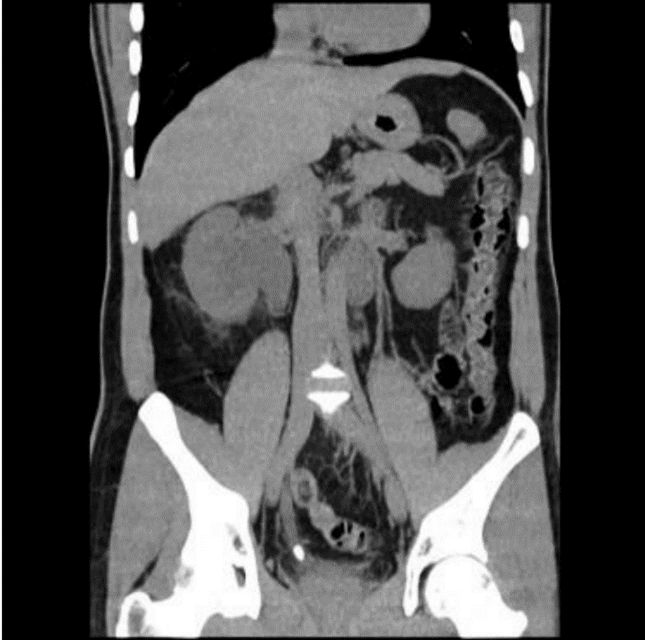

Sedan tidigare väsentligen frisk. Han uppsöker vårdcentralen pga. intervallartad högersidig smärta i flanken med utstrålning mot ljumsken. Jon remitteras till akutmottagningen pga. smärta, feber samt höga infektionsparametrar. Efter undersökning av Jon beställer jourhavande läkare undersökning med datortomografi.

Vad visar undersökningen?

A

• Stort konkrement mätande 15 x 9 mm distalt i höger uretär. Måttlig högersidig hydronefros samt hydrouretär.

o PUJ, vid kärlsträng, ostiet (innan urinblåsa)